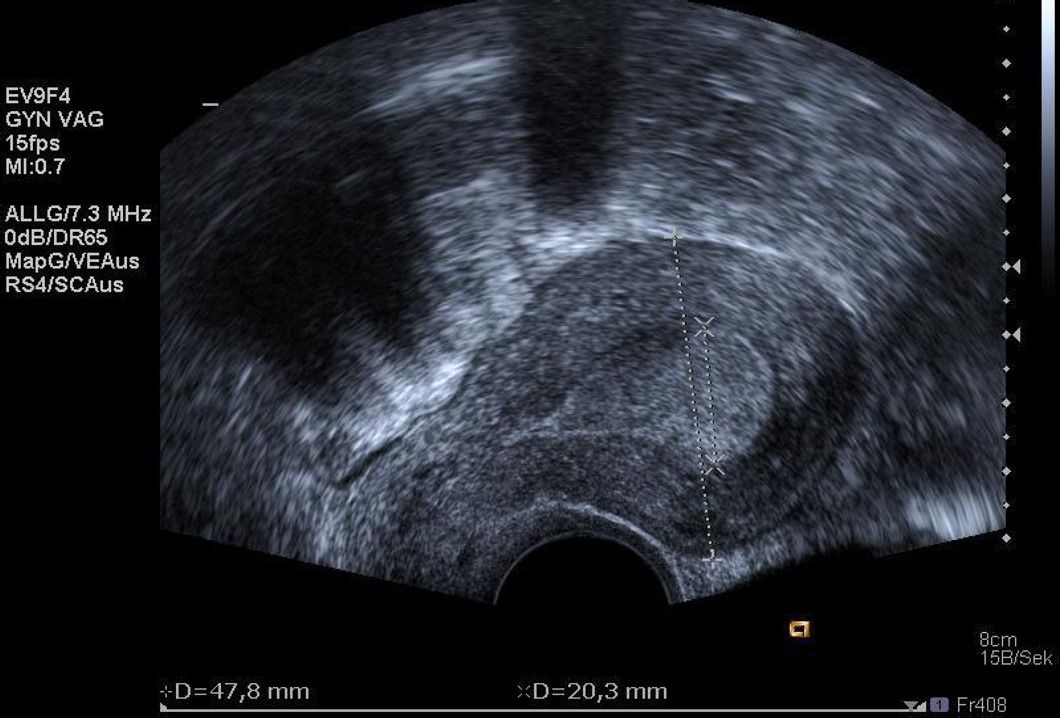

Die Diagnosestellung erfolgt in aller Regel mittels transvaginalem (durch die Scheide) Ultraschall. Nur in Ausnahmefällen ist eine MRT-Untersuchung notwendig.

Bei der Gebärmutterspiegelung wird die Gebärmutterhöhle mit Kochsalzlösung aufgedehnt. Eine Kamera mit integrierter Elektroschlinge wird in die Gebärmutter eingeführt. Die vorhandenen Myome können nun schrittweise unter Sicht abgetragen werden. Mittels modernsten Ultraschalluntersuchungen werden die Myome während der Operation noch einmal genau dargestellt. Bei sehr großen Befunden können zwei Operation zur kompletten Myomentfernung notwendig sein.

In Tübingen gehen wir mit den neuesten Entwicklungen der Medizin. So bieten wir auch die transzervikale Radiofrequenzablation (Sonata®) zur Myomverkleinerung an. Bei dieser Technik wird durch Einbringen einer speziellen Sonde durch den Gebärmutterhals das Myom per Ultraschall dargestellt und gezielt mit einer speziellen Elektrode punktiert. Über diese Elektrode wird mittels Strom Hitze erzeugt, die das Myom nachhaltig zerstört. Das geschädigte Myom wird in den folgenden Monaten vom Körper abgebaut und damit kleiner.